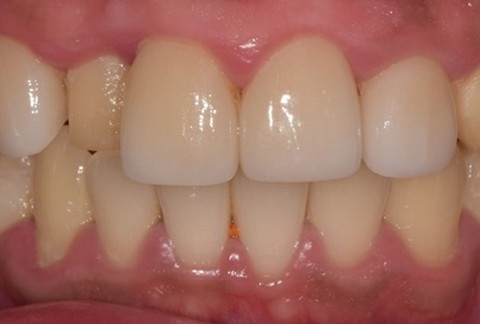

임플란트-보철-시-기성-어버트먼트가-아닌-맞춤-지대주-사용-보철-파절-위험-방지-음식물-끼임-방지-주위염-방지-맞춤-지대주는-환자의-구강환경에-맞는-교합을-구현할-수-있고-앞니-보철시-더욱-심미적으로-제작이-가능합니다

임플란트-전후사진